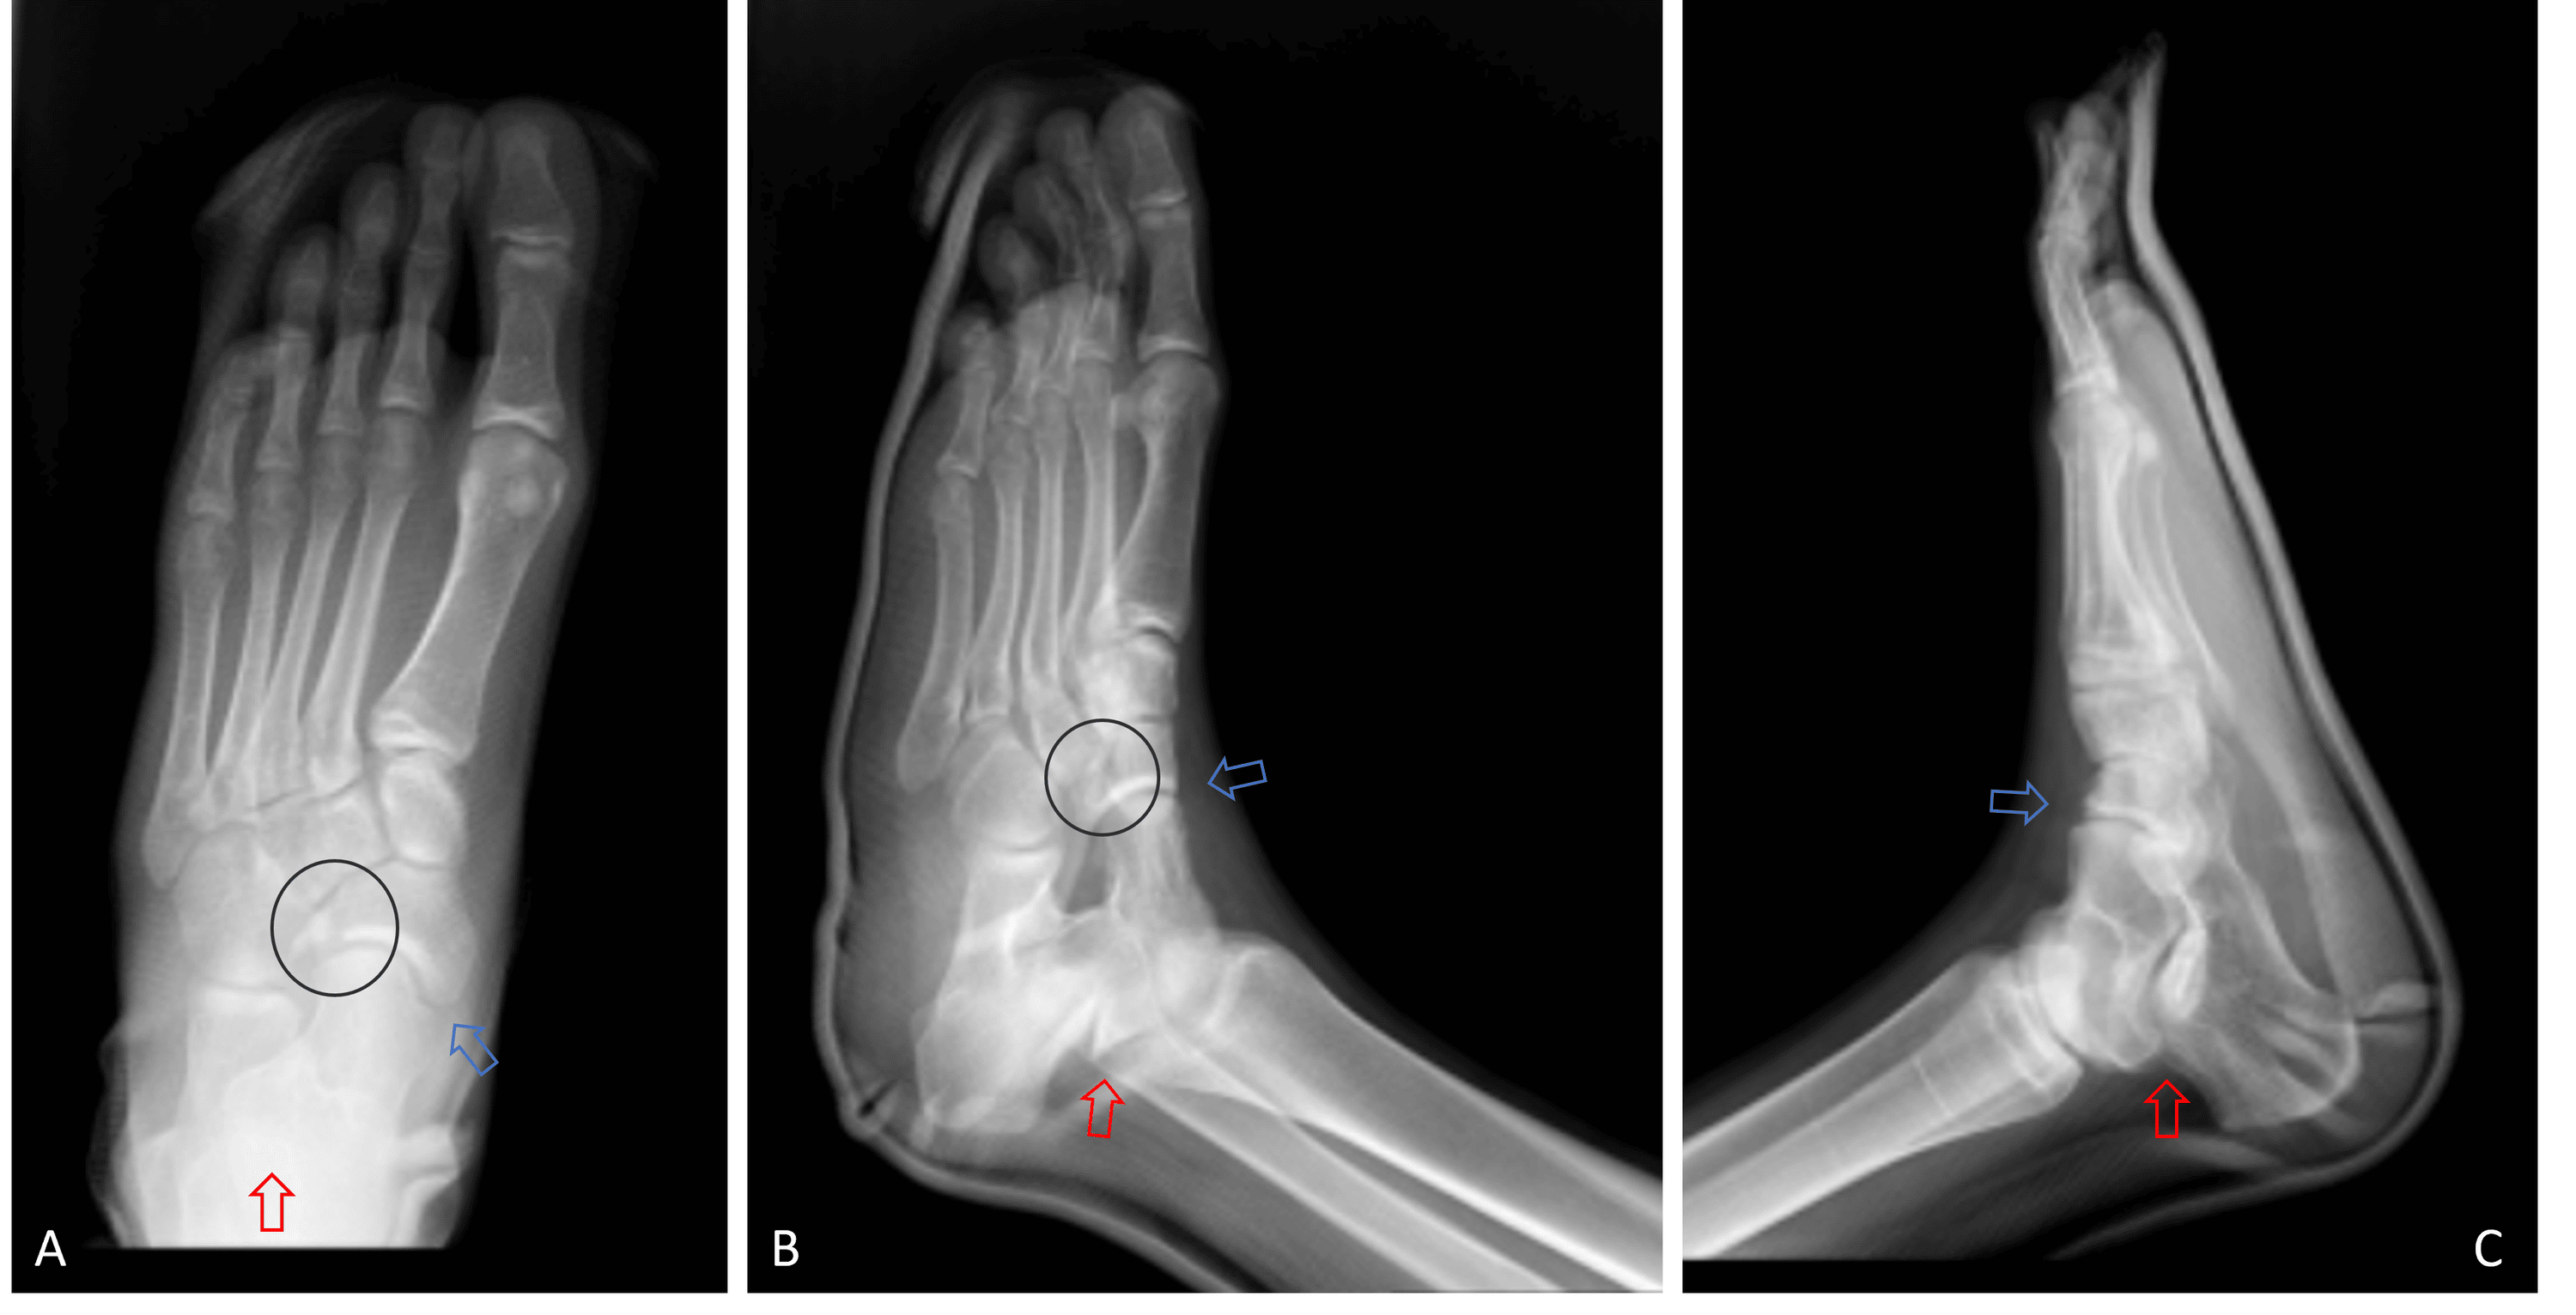

From www.cureus.com

Cureus Simultaneous Talocalcaneal and Talonavicular Joint Dislocation Can You Play Soccer With A Scaphoid Fracture — surgical management of scaphoid fractures can provide significantly improved rrs and rts to sport compared. symptoms of a scaphoid fracture typically include swelling and pain in the wrist just below the base of the thumb. early recognition of scaphoid fractures is crucial in helping an athlete have a successful outcome because of the risk of. . Can You Play Soccer With A Scaphoid Fracture.